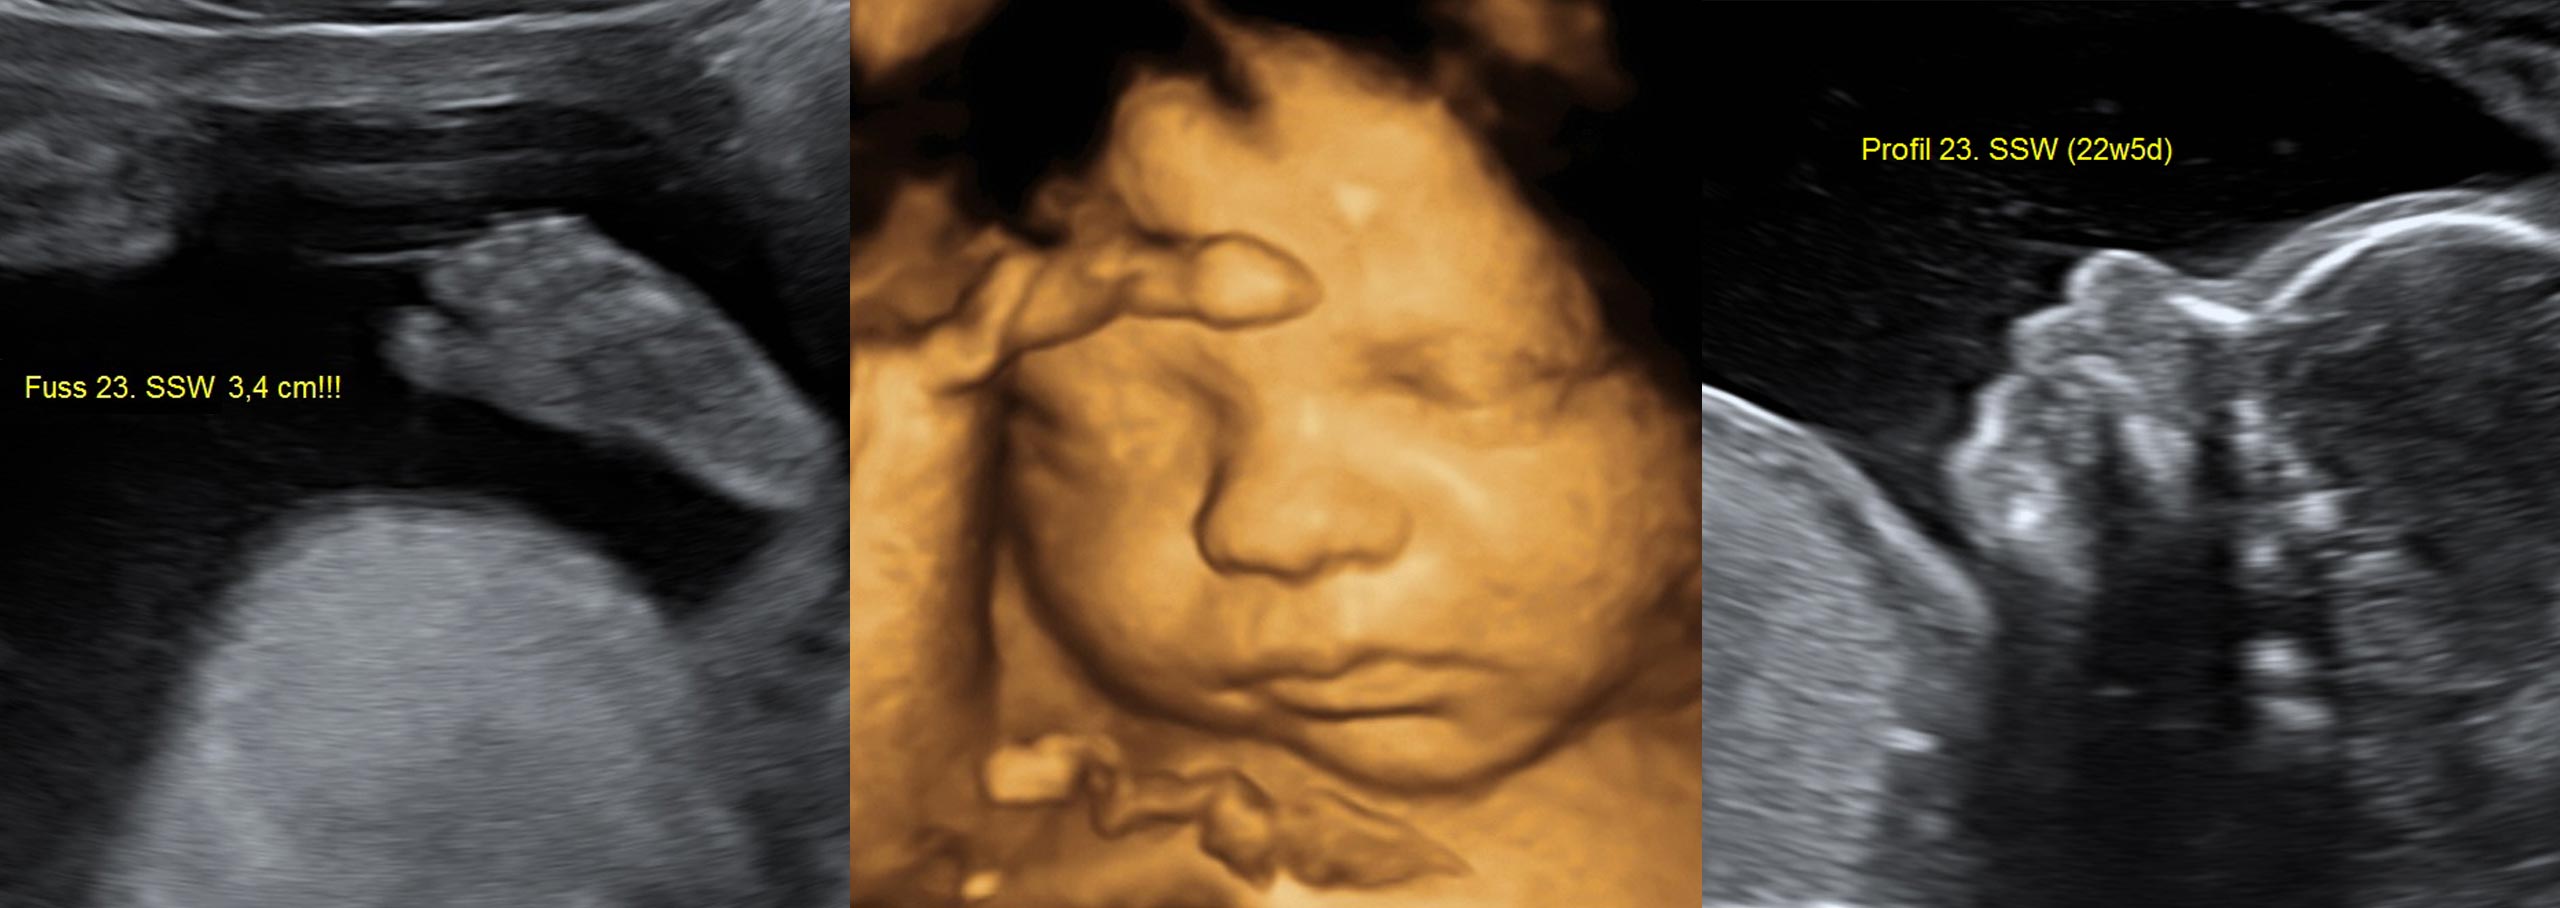

- 3D / 4D Ultraschall (24.-30. SSW)